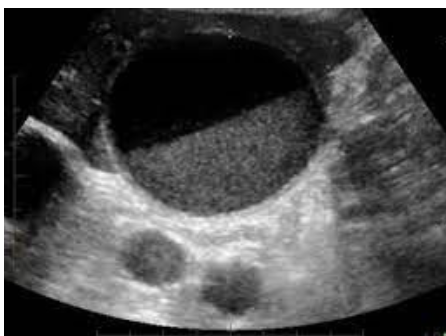

What pathology is in the image below

Sludge - Low level interal echoes, without shadows, no wall/ border